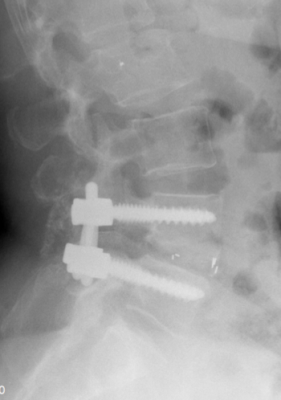

Stabilisierende Operationen

Zeigt sich ein höhergradiger Verschleiß bzw. eine ausgeprägte Instabilität, wird der betroffene Wirbelsäulenabschnitt versteift (Fusion). Kombiniert mit diesem Verfahren kann ggf. auch eine Erweiterung des Wirbelkanals (Dekompression) bei Verengung (Spinalstenose) erfolgen.